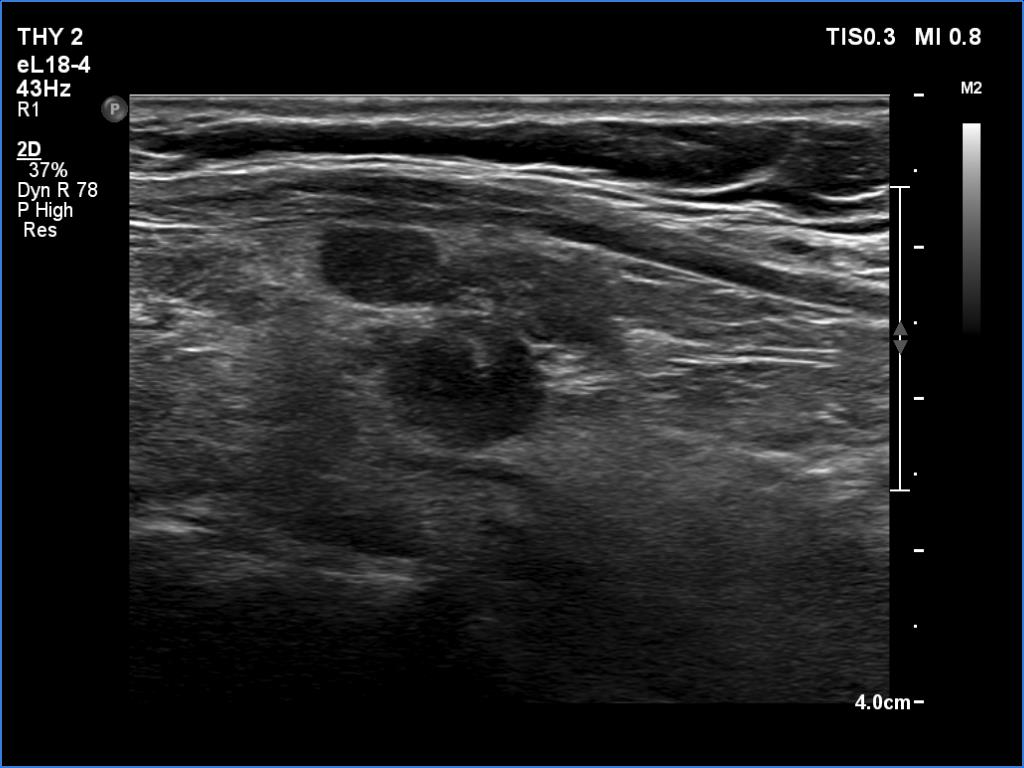

Ultrasonography. The thyroid was mainly composed of hypoechoic islets which floated in less hypoechoic background. These lesions had irregular, lobulated margins and showed no vascularity.

FNA was performed from a discrete lesion in the right and from another one in the left lobe. Cytology resulted in Hashimoto's thyroiditis. Wash-out thyroglobulin level exceeded 478 ng/mL in both cases.

Comment. The presentation was not entirely characteristic of Hashimoto's thyroiditis. Nevertheless, the multiplicity of the lesions, the irregular borders and the moderately hypoechoic non-lesional part of the lobe all argued for being these lesions not true nodules but more active foci of thyroiditis.